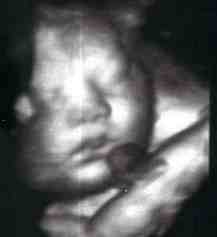

Вашето бебе сега е целосно развиено. Сите системи и органи функционират совршено.

Од оваа недела неговиот раст и качување на тежината нагло ќе опадне. Бебето до крајот на бременоста, само ќе вежба за животот надвор. Заради тоа што вежбањето на дишењето го прави со течност, наместо со воздух, можеби често ќе го чувствувате неговото икање.

Неговите коски се уште не се целосно отврднати. Тоа ќе го олесни чинот на раѓањето. Целосното стврднување на коските ќе се случи дури по породувањето.

Просечната должина на бебето сега е околу 48.5 см, а просечната тежина околу 2850 грама.

Бебе во 37-та седмица на бременост